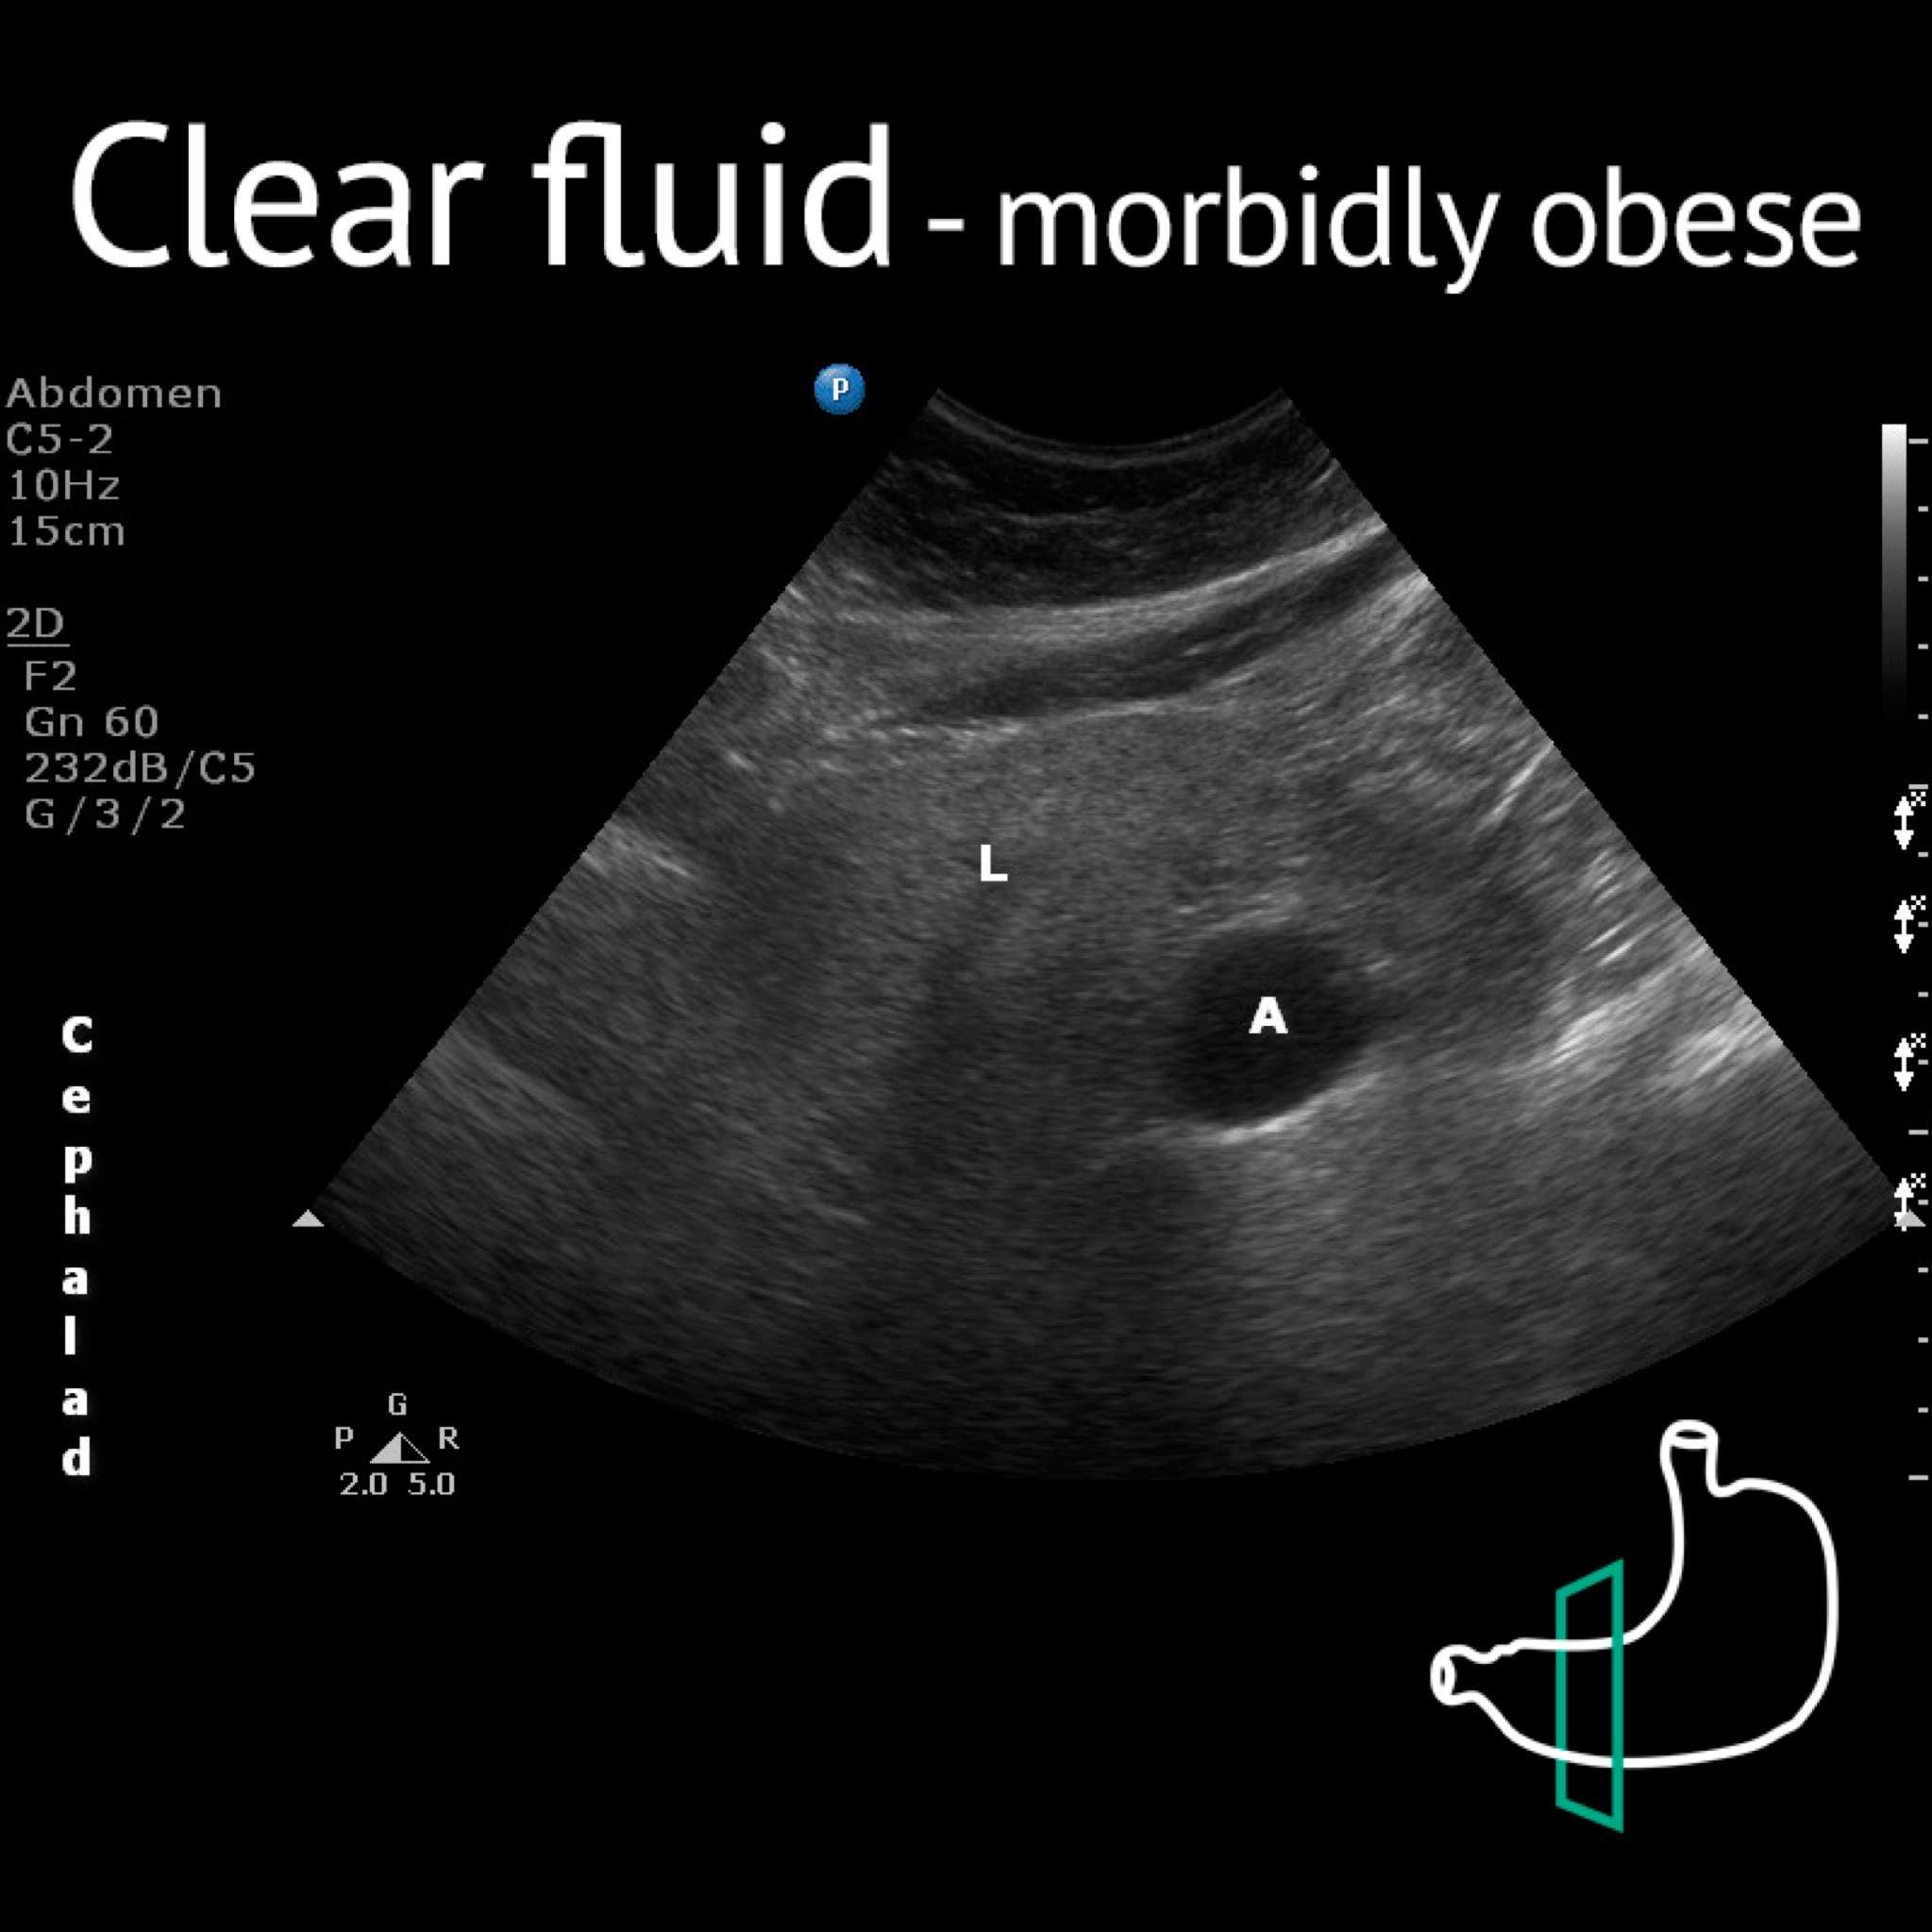

A: antrum; Ao: Aorta; L: liver; P: pancreas; Sma: superior mesenteric artery